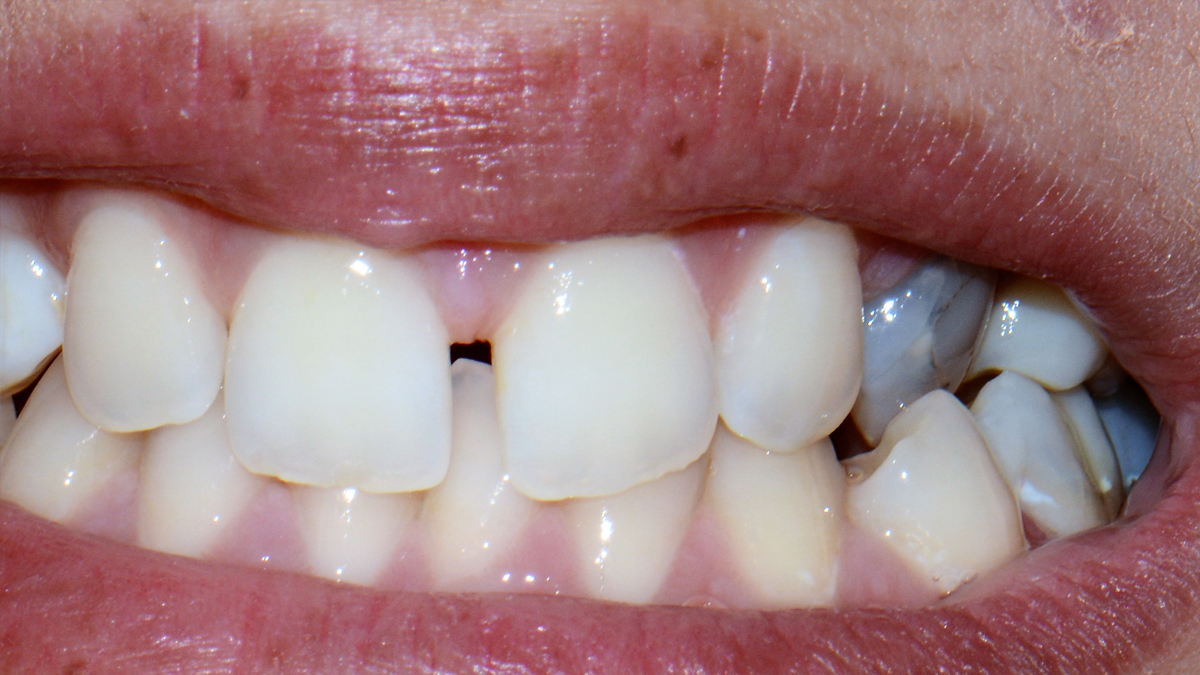

A tömőanyag tulajdonságaiból adódóan ma már, ha az üreg nem túl nagy, minden fogcsoport tömésére alkalmazható. Rágófogakban képes helyreállítani a funkciót, azaz egy erős, a rágóerőkkel szemben ellenálló tömés készíthető, frontfogakba (metszőfogak) pedig készülhet olyan esztétikus, észrevehetetlen tömés, mely kedvezően befolyásolhatja megjelenésünket, arckarakterünket.